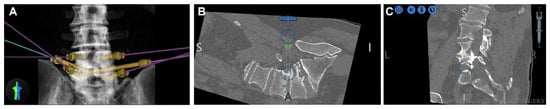

- Park, C.; Crutcher, C.; Mehta, V.A.; Wang, T.Y.; Than, K.D.; Karikari, I.O.; Goodwin, C.R.; Abd-El-Barr, M.M. Robotic-assisted percutaneous iliac screw fixation for destructive lumbosacral metastatic lesions: An early single-institution experience. Acta Neurochir. 2021, 163, 2983–2990. [Google Scholar] [CrossRef] [PubMed]